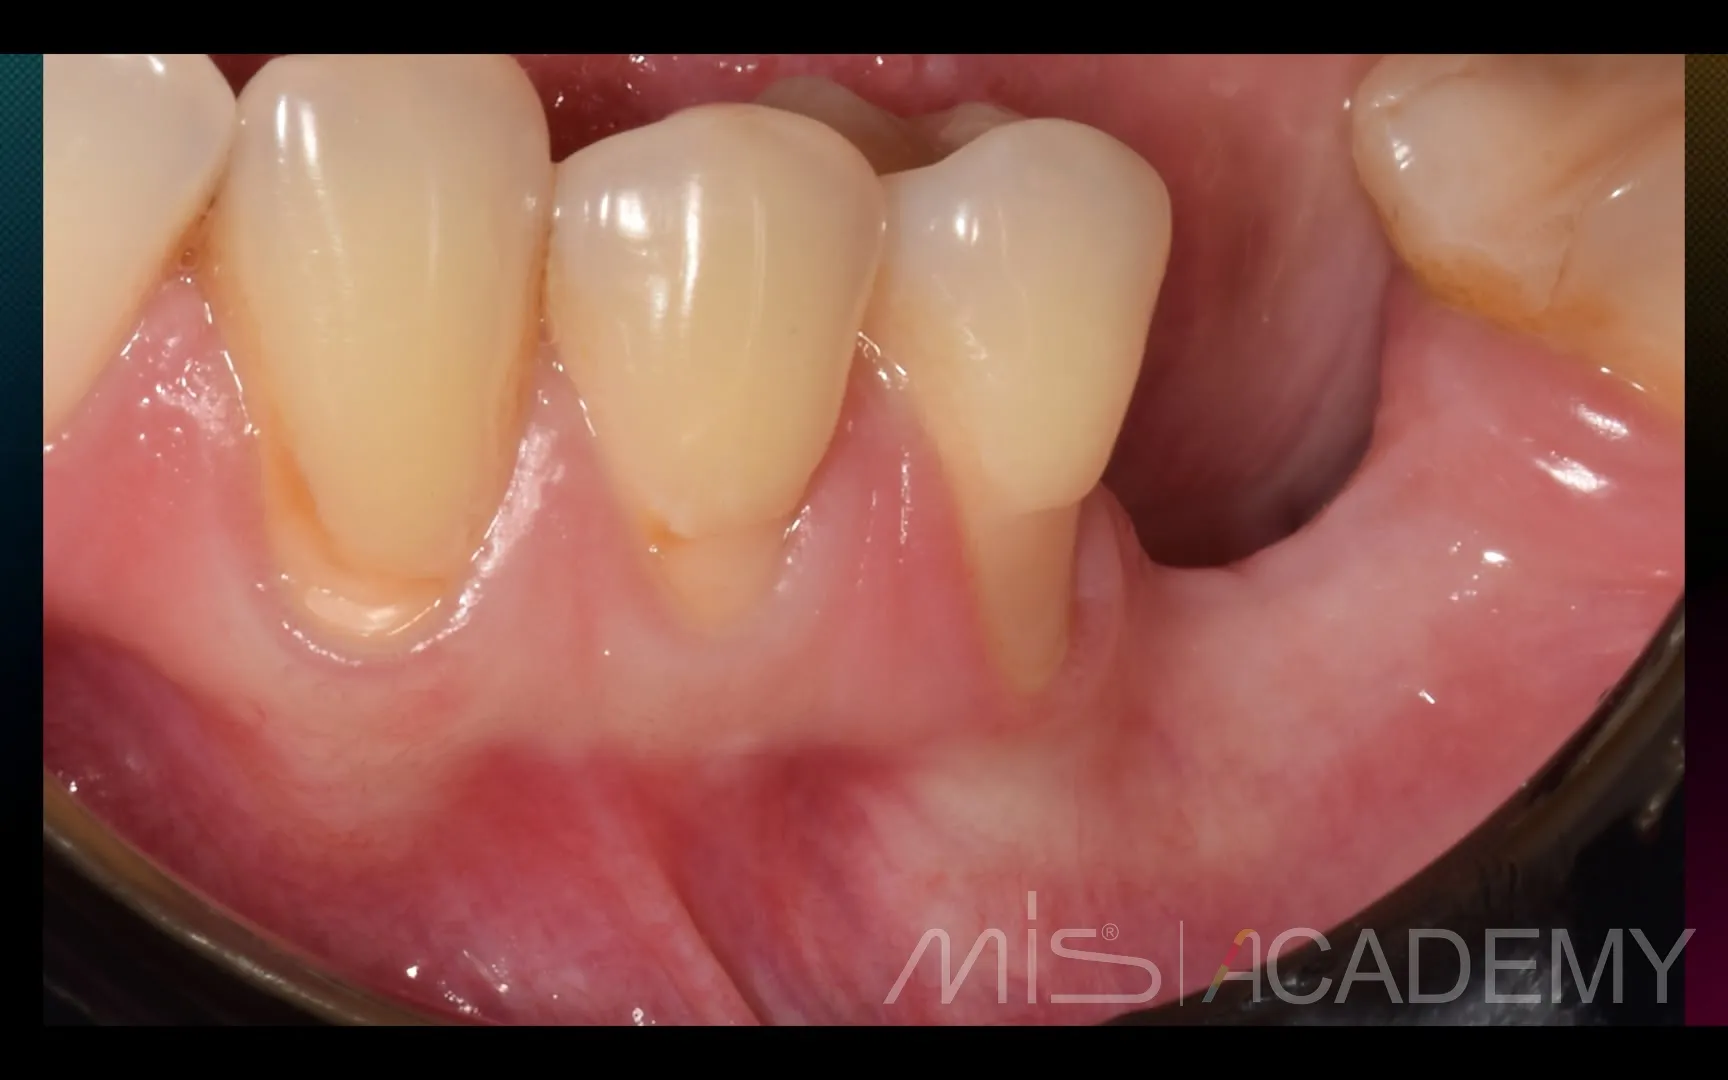

Промежуточный результат клинического кейса одномоментного закрытия рецессий и установки имплантата MIS C1 с CONNECT абатментом.